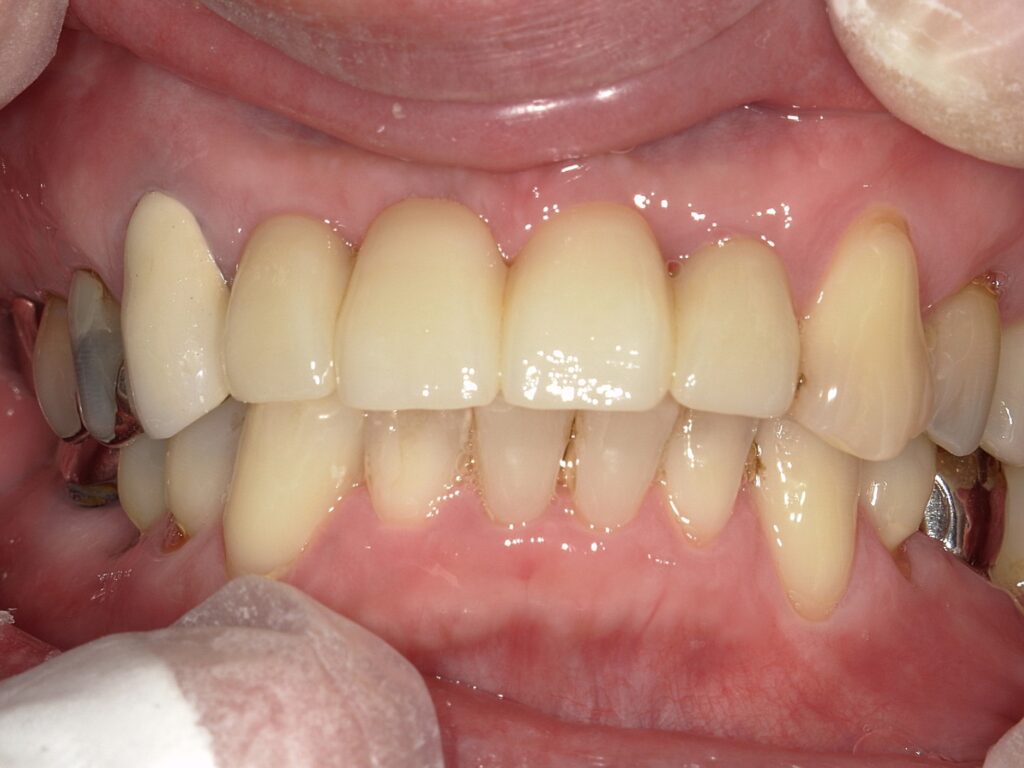

どうでしょうか、

自然な感じで、ほぼご自分の歯としてもよいほどでしょう。

上がインプラント後3か月めです。4か月後には歯が入りました。

下が装着したところ。